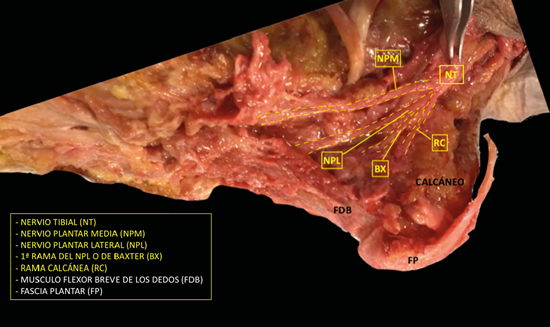

El nervio tibial, en su tránsito por la cara medial del tobillo y del pie, dará las ramas calcáneas mediales, el nervio plantar medial, el nervio plantar lateral y la primera rama del nervio plantar lateral o rama de Baxter3. El nervio peroneo profundo se localiza en profundidad a la musculatura extensora del primer radio a la altura del tobillo. El nervio peroneo superficial discurre por el borde anterior del peroné para llegar escindido al tobillo en los nervios cutáneo dorsal medial y cutáneo dorsal intermedio. El nervio sural, situado en el aspecto posteromedial de la pierna adyacente a la vena safena menor, dará las ramas calcáneas laterales antes de girar retromaleolar al peroné hacia el pie para denominarse como el nervio cutáneo dorsal lateral (Figuras 2 y 3)2,3.

Figura 2. Imagen de disección del nervio tibial y sus ramas.

Figura 3. Túnel tibiotalocalcáneo. El nervio tibial (NT) se divide en la rama calcánea (RC), el nervio plantar medial (NPM) y el nervio plantar lateral (NPL) del que se escinde la rama de Baxter (RBx). Las estructuras musculotendinosas tibial posterior (TP), flexor largo del primer dedo (FLD) y flexor largo de los dedos (FCD) acompañan al nervio tibial en su recorrido por la cara medial del tobillo y el pie. Imagen modificada de la App Ankle & Foot Pro III.